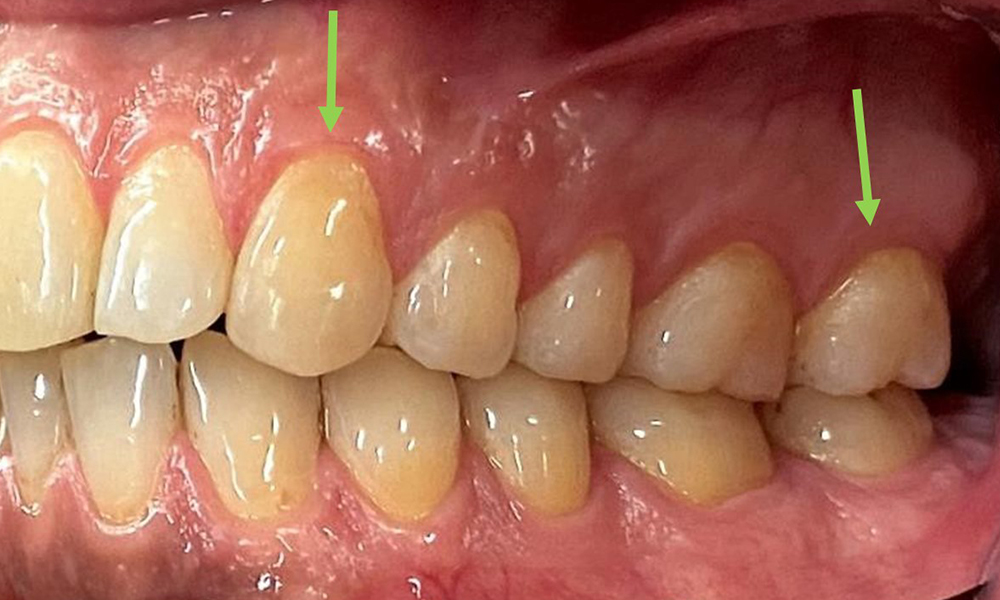

Adâncimile clinice de sondare se situau în intervalul 1-3mm, în limitele fiziologice. S-au observat recesiuni maxilare de până la 1 mm, de la 13 la 16 și de la 23 la 27. BOP a fost de 15 %.